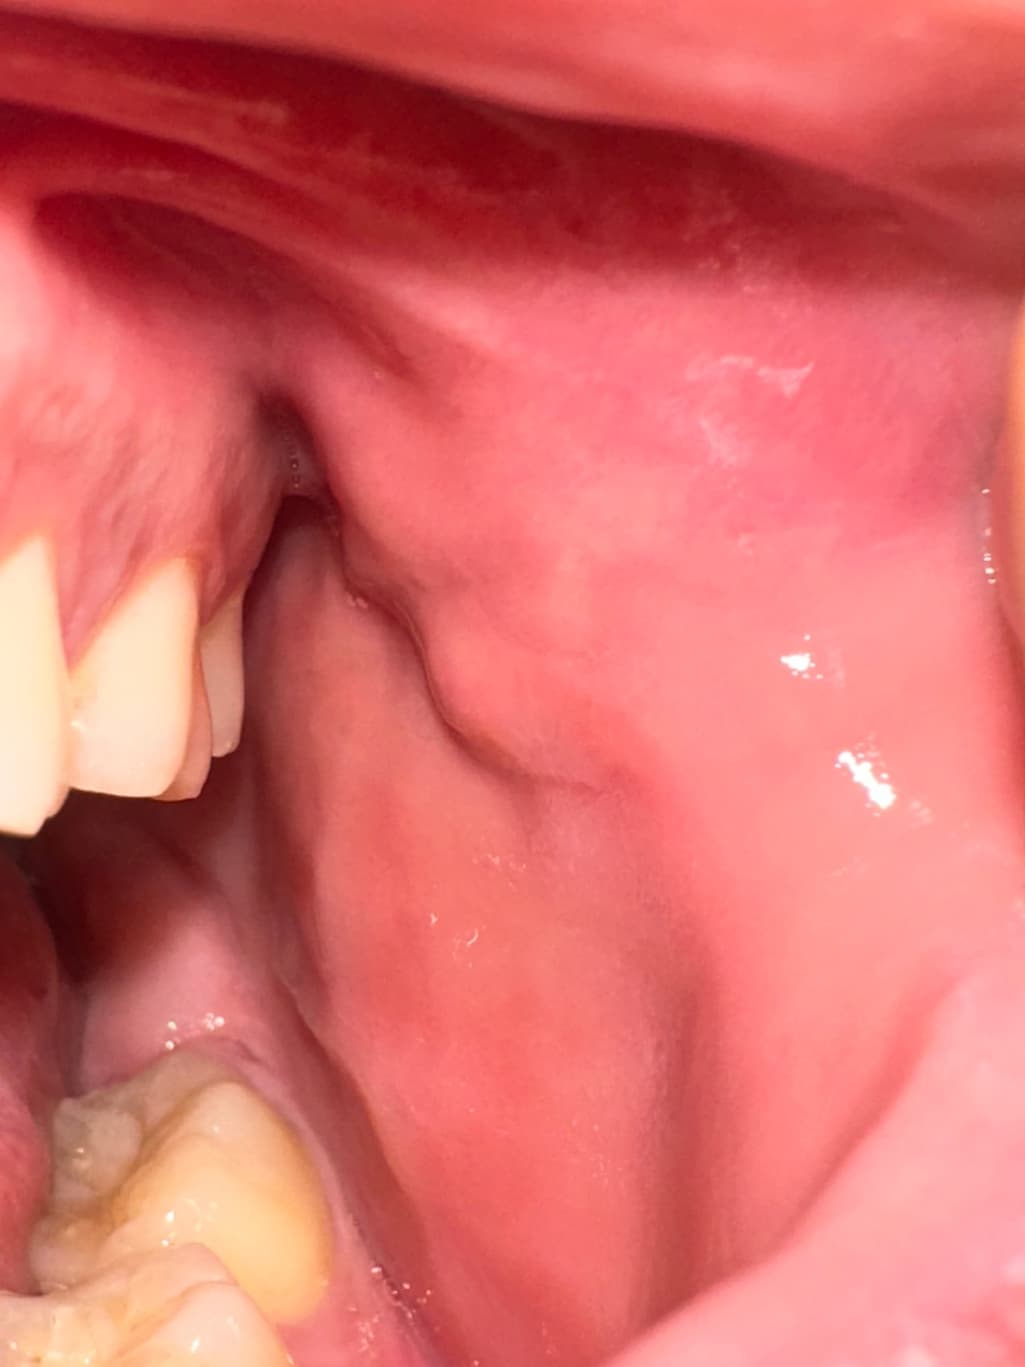

구강내 우측 상당 어금니 부분 옆 볼살에 이질감이 느껴집니다

안냥하세요 평소에도 좌측과 우측 동일하게 혹 비스무리흔디 잡히고 그랬었습니다 다만, 이틀 전 부터 우측 부분이 붓고 평소보다 살짝 더 심하게 느껴지는 것 같았슺니드 이게 정살일가료? 참고로 흡연 11년 하루 8개이며 나으ㅡㅡㅡㄷ

• 4번 째 사진

볼살이 치아에 씹혀서 부종이 생긴거 같습니다. 큰 문제가 잇는건 아니니 너무 걱정하지마세요.

사진으로는 특별한 문제가 보이진 않습니다. 점막 조직에 자극이 많이 되었을 경우 불편한 감각이 있을 수 있으니 흡연으로 인한 점막 조직의 자극을 줄이는 것이 좋을 것으로 생각됩니다.

해당 부분은 단순히 볼이 씹혀서 그럴 가능성이 높습니다. 치과가서 검사 받아보심이 좋아보입니다.